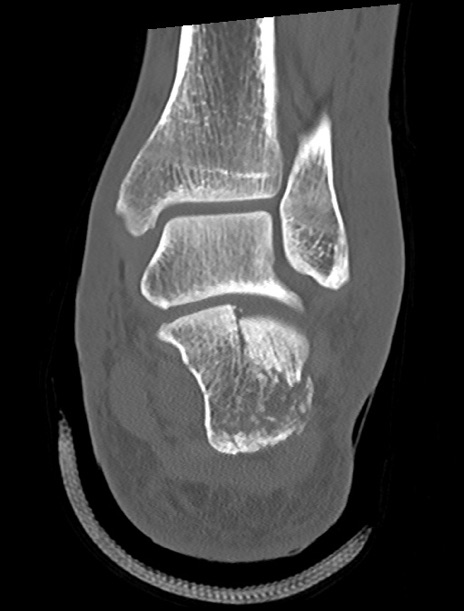

症例37 左足関節CT(冠状断像)

左足関節CT

矢状断像